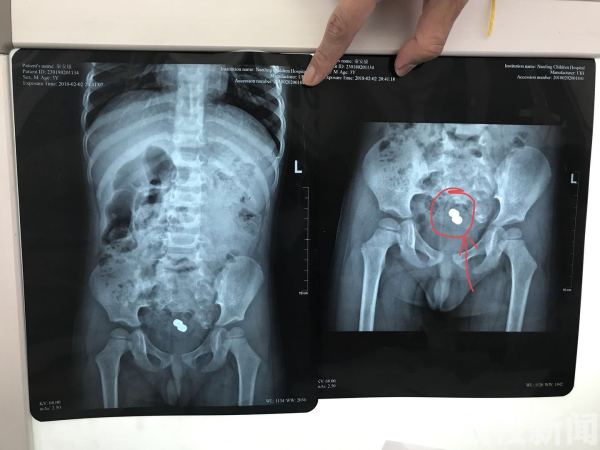

康康妈妈觉得塞入肛门也没有关系,说不定过两天解大便的时候解下来呢,于是就没有当回事情,还不停的给他吃东西,指望多点大便解下来。可是一连几天康康光吃东西,就是不解大便,肚子鼓鼓的,奶奶知道情况后,居然用手扣,不但没有扣出来,反而肛门口还出血了,孩子被折腾的捂着肚子喊痛,妈妈这下也就着急了,赶紧带着他到当地的医院看一下怎么回事,当地医院由于没有专业的儿科,只是拍了一个腹部平片,X片显示在康康的肚子里面有一个不规则的玩具,由于没有儿童肠镜,医生建议他到南京医科大学第二附属医院就诊。家里人赶紧前往,接诊的南京医科大学第二附属医院儿童消化内科主任盛伟松,他接诊后发现康康的腹部X片也显示有一个玩具的,肚子也是鼓鼓的,肠鸣音也很弱,随即收入院进行肠镜检查。

入院后的康康,在肠道准备和相关检查完成后,康康被送到了儿童胃肠镜室进行检查。盛主任亲自为他做了肠镜,就在镜子进去的时候,康康的结肠里全都是大便,由于时间长都成球状,肠镜进去的时候视野很不好,必要要把大便弄出来,但是凭着肠镜一点点的弄大便,会造成麻醉时间过长。为此盛主任通过生理盐水冲洗肠道,积聚了好几天的大便软化了,排出来了,整个肠镜室充斥着刺鼻的臭味,此时肠镜发现玩具卡在了肠腔里面,通过肠镜的活检夹无法搞动,如果硬拽的话,万一刺破肠道,后果也很严重,为此盛主任决定使用卵圆钳深入肛门,在肠镜的引导下,小心翼翼的将卡在肠腔的玩具夹出来,旁边的麻醉师和护士都开玩笑称盛主任是新时代的“时传祥”。

“我们科每年都要碰到多例孩子吞食异物的,经过胃镜取出,但是碰到这么小的男孩,肛门被自己塞入玩具还真是见的不多。”儿童消化主任盛伟松介绍到,盛主任说康康的事情指出,小孩才三岁,由于不懂事,由于平时都有使用开塞露的习惯,所以好奇把不规则形状的玩具往肛门里塞,而且还很深,其实是非常危险的,还有家长总觉得能够排出来,但是由于肠道的弯曲和生理的狭窄使异物卡住了,很难自行排出,而且肠壁很脆弱,稍不关注就会被戳破,一旦引起肠穿孔,肠道里的排泄物就会通过漏洞跑到腹腔里导致腹膜炎,这将是致命的,由于大便积聚太多,麻醉时间有不能太长,操作比往常更具有挑战性,最后我们小心翼翼的快速的将大便弄出后,通过卵圆钳成功的夹出来,毕竟小孩受更大的痛苦。提醒家里有小孩的市民,一定要看管好孩子,一旦发现吞食或者塞入嘴巴,鼻腔和肛门异物的时候,要及时到医院就诊,不要贻误治疗。